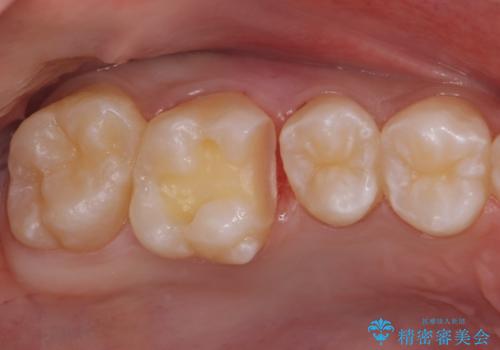

歯と歯の間の虫歯 セラミックインレーでの治療

- 検査の結果、レントゲン画像上で虫歯が確認されたため治療をしていくこととなりました。

白くて精度の高いものをご希望されたためセラミックインレーでの治療を行いました。

- 右上6 セラミックインレー 77,000円費用は治療当時の料金となります

小さな段差もないような適合の良い修復物は他の修復物に比べて今後の虫歯リスクを抑えることができます。